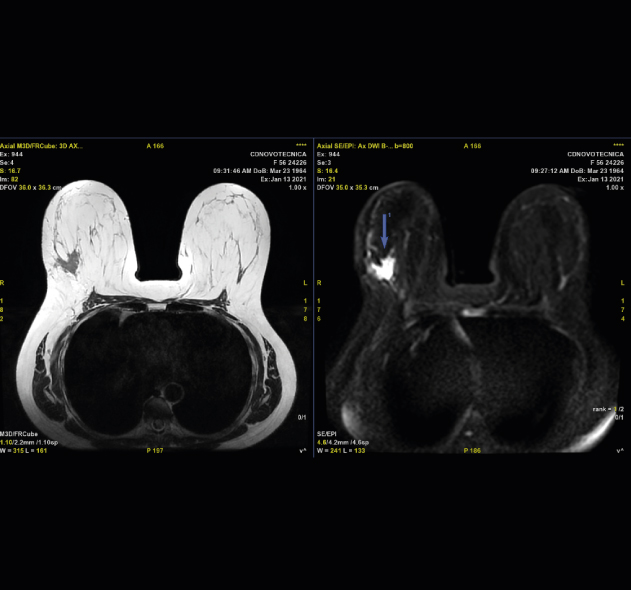

DIFUSIÓN

Clásicamente se empezó a usar la difusión en el estudio del sistema nervioso central y en la actualidad es una secuencia estándar en el estudio cerebral. Inicialmente permitía valorar la isquemia cerebral, pero en la actualidad sus usos son muy diversos, permitiendo también valorar enfermedad neoplásica, patología inflamatoria e infecciosa. En el resto del cuerpo humano básicamente se estudian lesiones tumorales y ayuda en diferenciar lesiones malignas de benignas. Está establecido ya su uso en mama, en próstata y también empieza a utilizarse en otros órganos, por ejemplo, hígado, ovario y útero. Últimamente se está usando como rastreo general en busca de tumores, especialmente metástasis, simulando un PET; es lo que se denomina RM-difusión corporal.

Difusión de mama